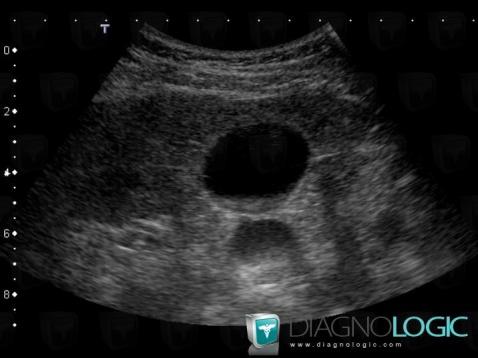

Sludge, Gallbladder, US

- Diagnosis Sludge, Location(s) Gallbladder, with gamuts Intravesicular lesion